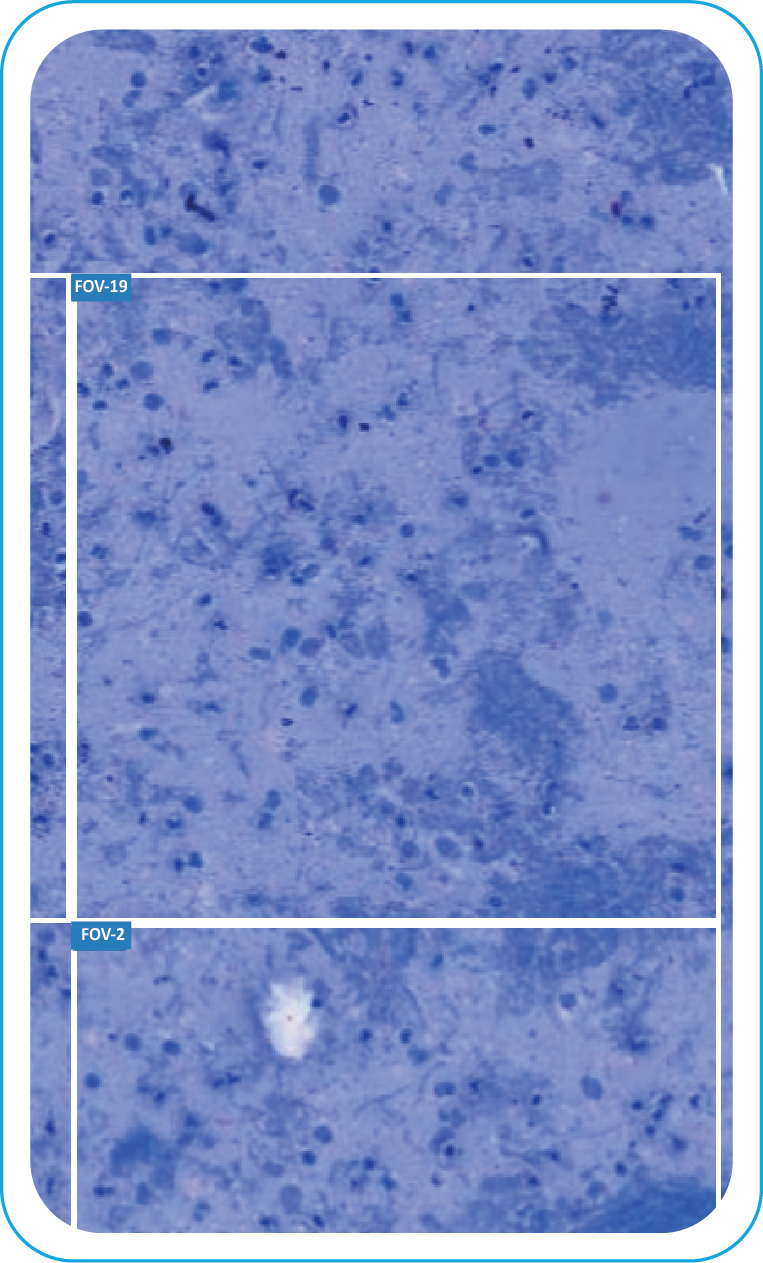

During acquisition, BactoSiA AI performs automated slide triage, marks FOVs, and triages slides as "likely negative" or "likely positive" to prioritize pathologist review. Confirmed positive smears are graded using standardized criteria aligned with WHO guidelines. All images and reports are managed digitally in IMAGEPath® software

Brightfield Smear Overview

FOV Generated

Clear FOV

Visible Bacilli

with Annotations